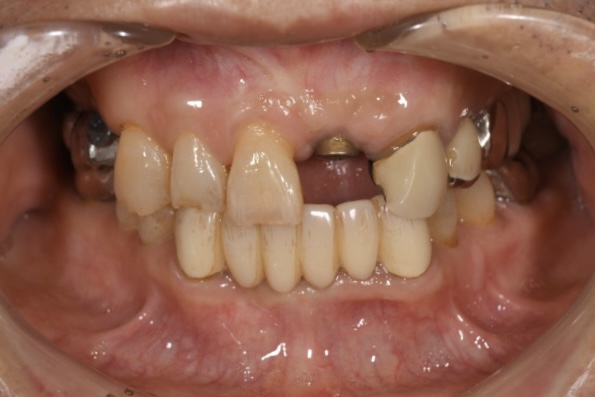

前歯のインプラント治療をする際、審美的に一番大切なのは両隣の歯との歯茎のラインをそろえることとなります。

両隣より歯が長くなってしまうと、大きく歯を見せて笑った時などに不自然にみえてしまいます。

インプラント埋入する場合は大体が状態の悪い歯を抜歯してからのインプラントとなります。

状態の悪い歯はほぼ骨吸収が起こっていますが、インプラントの被せ物と両隣の歯との歯茎のラインを合わせるためには骨の高さが重要となるため、だいたいの症例でGBR(骨造成)が必要となります。

この症例もインプラント埋入時に骨造成を行っています。

見た目だけでなくインプラント治療を行う際は、しっかりと骨がある事、なければ骨を作ることが大切です。